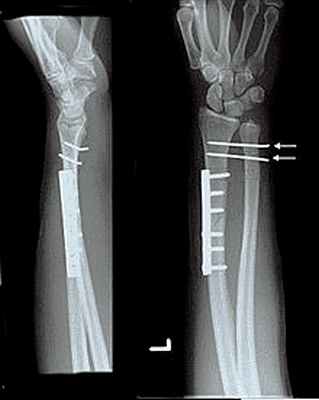

106. Переломы дистального отдела костей предплечья

Остеосинтез при переломах дистального отдела лучевой кости производят редко, как правило, при неудаче консервативного лечения. Для остеосинтеза применяют малую Т-образную пластину (Рис. 140).

Первый винт вводят через продолговатое отверстие в проксимальный отломок, тем самым создавая опору для дистального фрагмента. Сам отломок фиксируют компрессионным спонгиозным винтом через отверстие пластины. Рану ушивают с тщательным восстановлением квадратного пронатора. Движения в лучезапястном суставе разрешают через 3–5 дней.

Остеосинтез лучевой кости в дистальном отделе